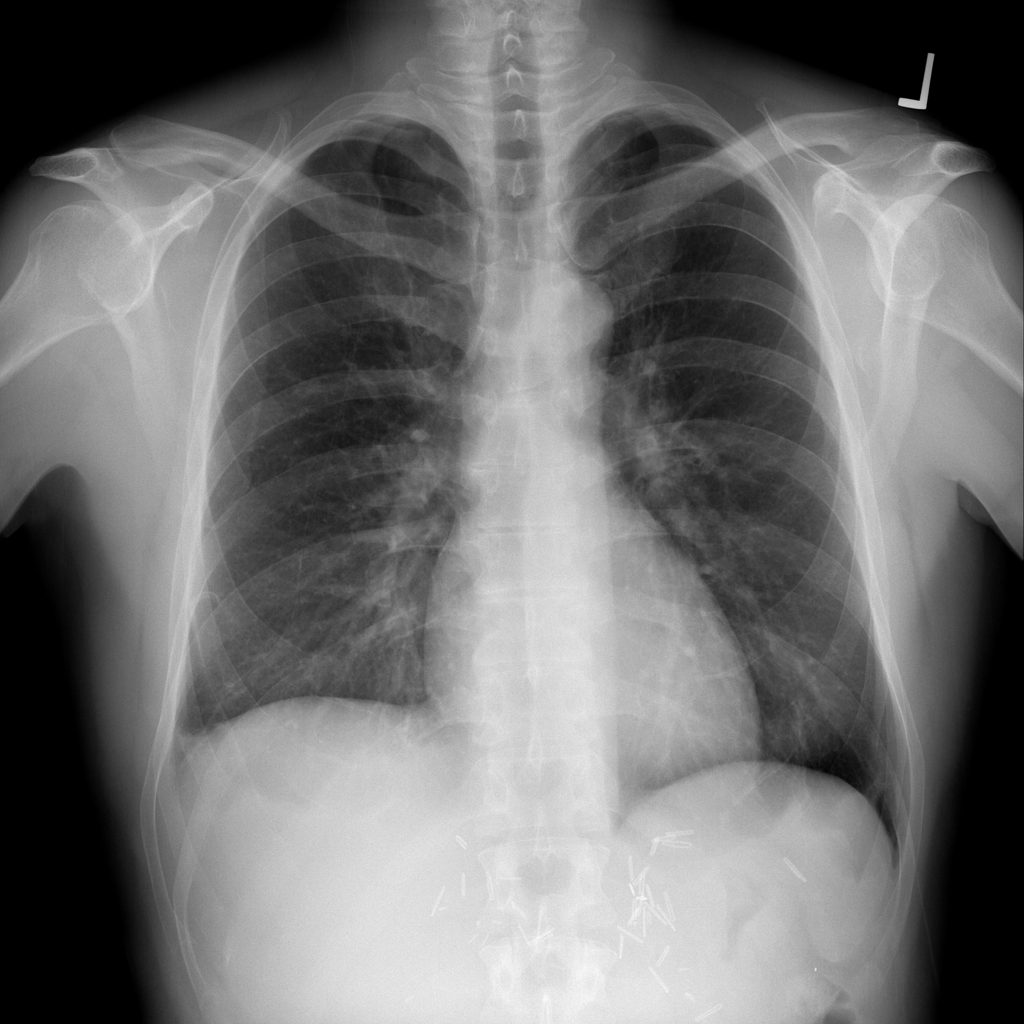

PAT-E066 · IMG-010Fibrosis

PAT-E066 · IMG-010

PA